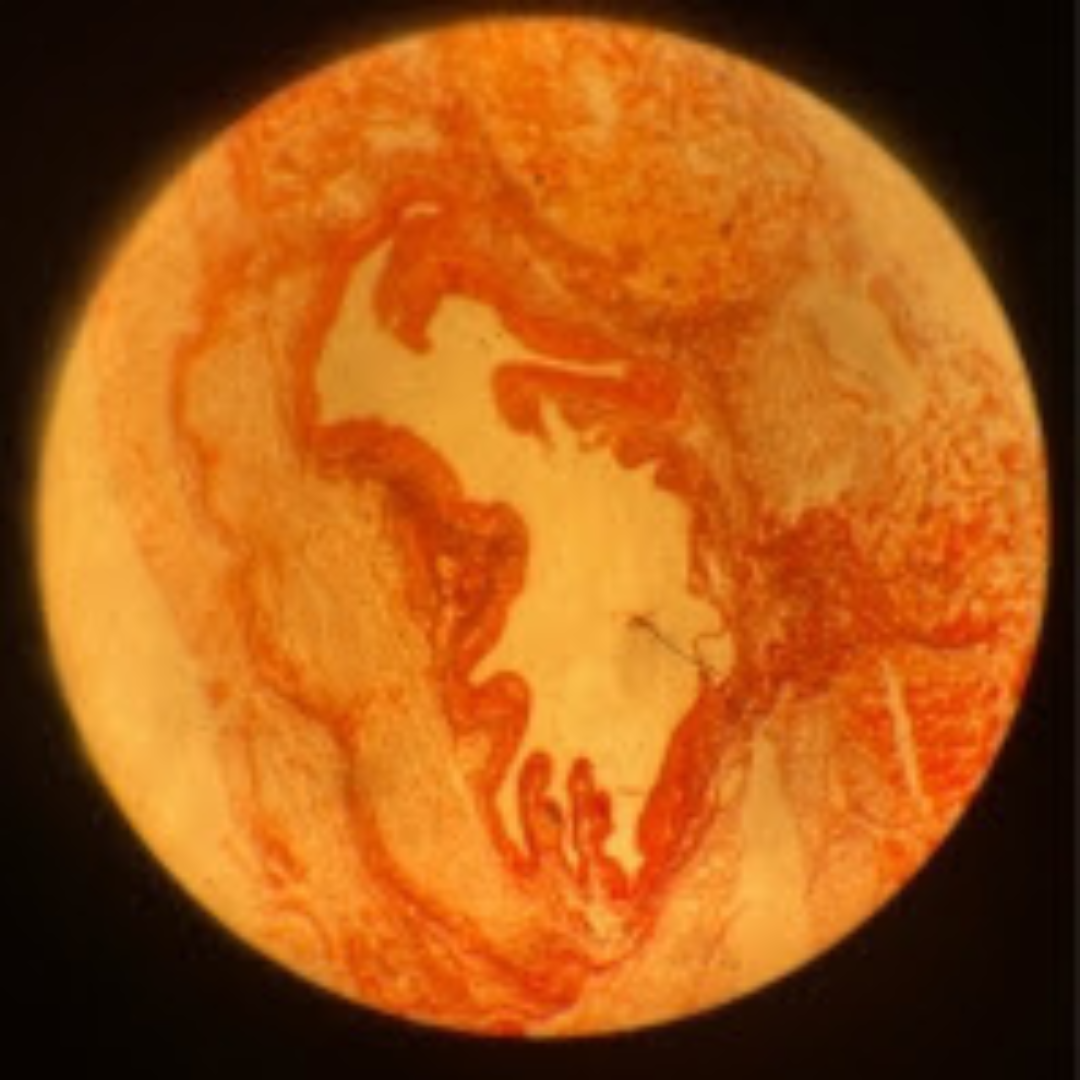

Elastic Arteries (Aorta)

Elastic Arteries (Aorta)

Elastic Arteries (Aorta)